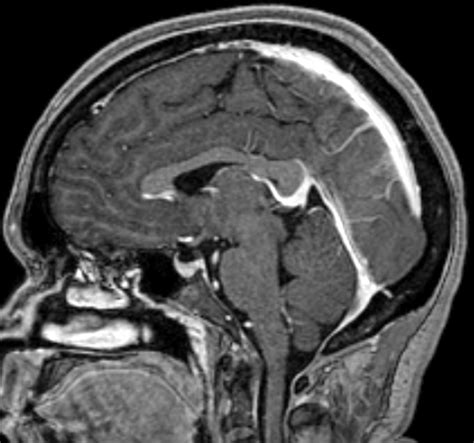

Preoperative imaging, including magnetic resonance venography (MRV) and computed tomography venography (CTV), can help identify the Inferior Sagittal Sinus and plan the surgical approach accordingly.

Diagnostic Imaging

Diagnostic imaging plays a crucial role in evaluating the Inferior Sagittal Sinus. Techniques such as MRV and CTV provide detailed visualization of the venous sinuses, allowing for the detection of abnormalities and pathologies. Common pathologies that can affect the Inferior Sagittal Sinus include:

Diagnostic imaging is the cornerstone of evaluating the Inferior Sagittal Sinus. The following imaging modalities are commonly used:

• Magnetic Resonance Venography (MRV): Provides detailed visualization of the venous sinuses without the use of ionizing radiation. It is particularly useful for detecting thrombosis and other venous abnormalities.

• Computed Tomography Venography (CTV): Offers high-resolution images of the venous sinuses and is useful for detecting acute thrombosis and other pathologies.

• Digital Subtraction Angiography (DSA): Provides real-time visualization of the venous sinuses and is often used for interventional procedures.